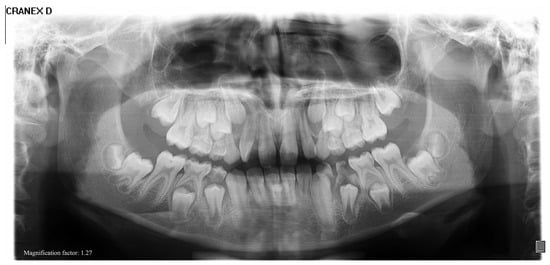

| 1 | Male | 48 | Osteoma of the coronoid process |

OPG CT | 19 mm | Coronoidectomy | 39 mm |

| 2 | Female | 10 | Bilateral hyperplasia of the coronoid processes |

OPG CT | 17 mm | Bilateral coronoidectomy | 45 mm |